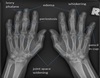

What hand signs may be present in someone with rheumatoid arthritis? (4)

What changes may be seen on XR in someone with rheumatoid arthritis? (4)